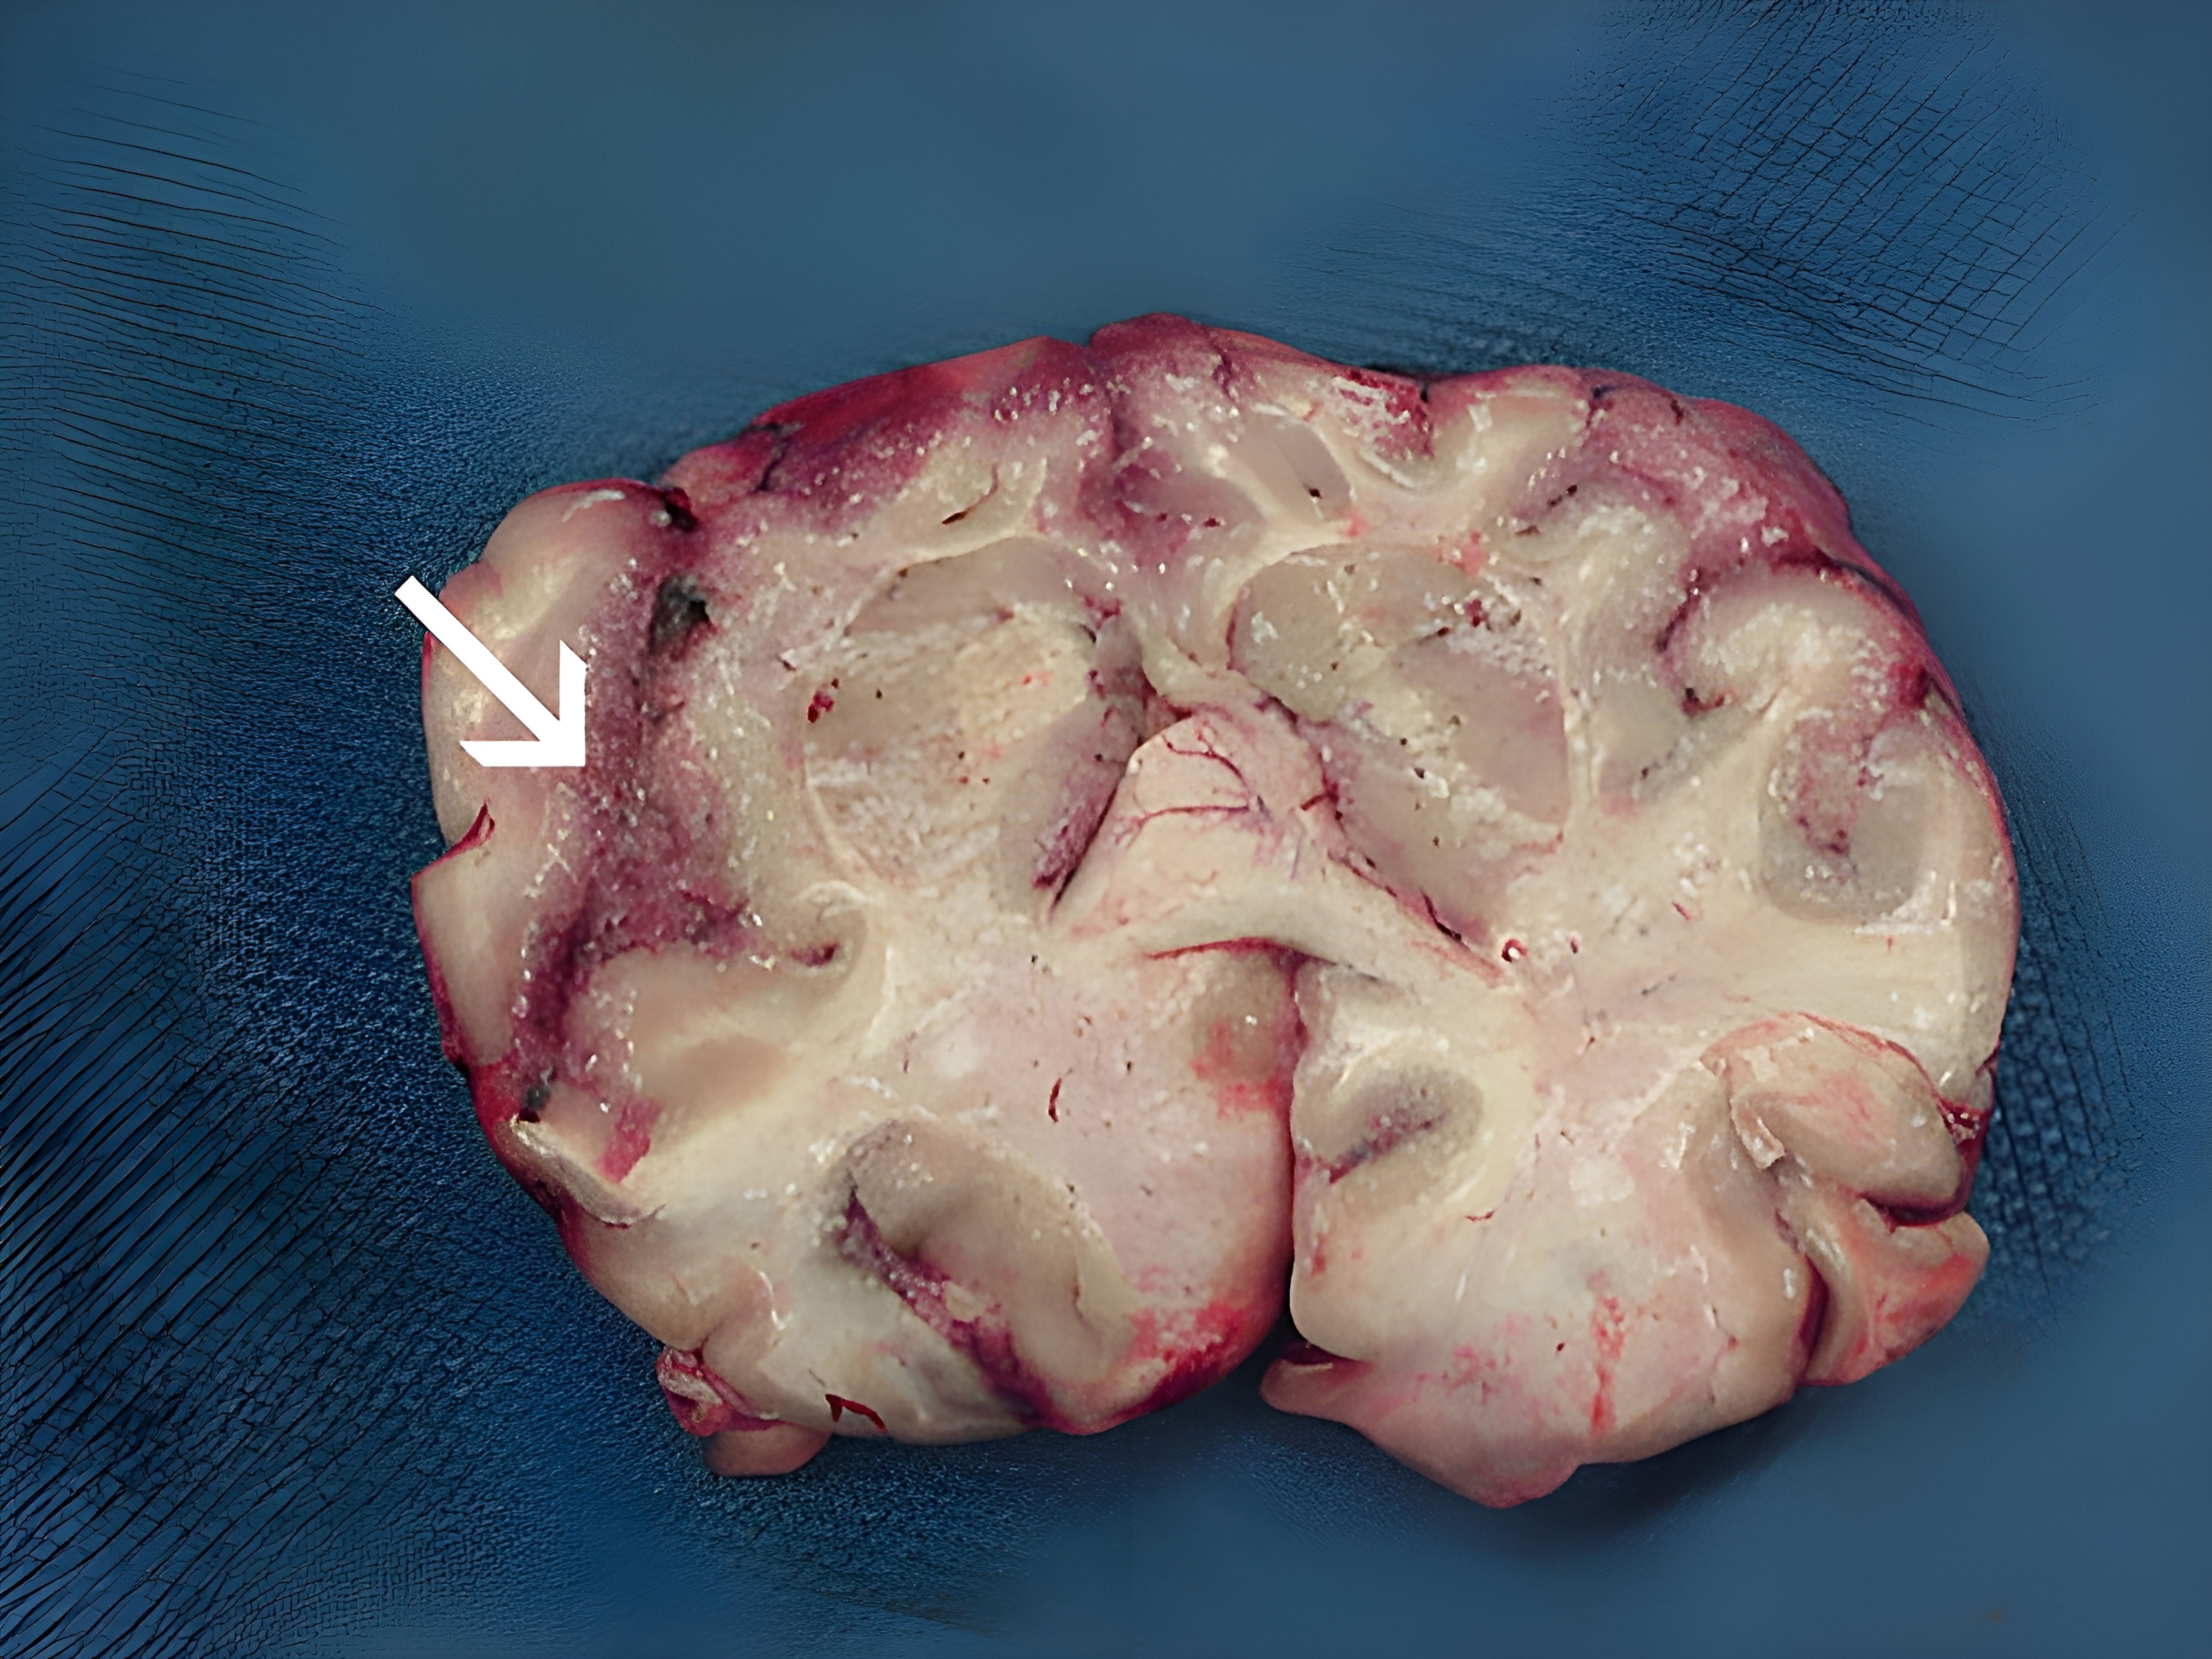

Im südindischen Bundesstaat Kerala schlagen die Behörden Alarm wegen zunehmender Todesfälle durch eine das Gehirn zerstörende Amöbe. Zwar seien die Fallzahlen immer noch sehr niedrig, die Zahl der Todesfälle habe sich im Vergleich zum vergangenen Jahr aber verdoppelt, erklärten die Behörden am Donnerstag. Demnach wurden seit Jahresbeginn 72 Infektionen mit der Amöbe Naegleria fowleri registriert und 19 Todesfälle. 2024 waren es demnach 36 Infektionen und neun Todesfälle.

Nach Angaben der US-Gesundheitsbehörde CDC wird Naegleria fowleri oft als "hirnfressende Amöbe" bezeichnet, weil sie das Hirn befallen und Hirngewebe zerstören könne. Wenn die Amöbe das Gehirn eines Menschen erreicht, kann dies demnach eine Infektion verursachen, die in 95 Prozent der Fälle tödlich ist. Naegleria-fowleri-Infektionen seien "sehr selten, aber fast immer tödlich", heißt in in den CDC-Erläuterungen.